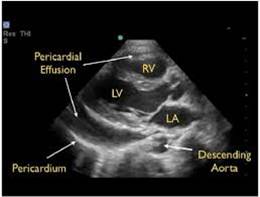

- The parasternal long axis view can be helpful in distinguishing between pericardial (anterior to descending thoracic aorta) and pleural (posterior to the DTA) effusions.

- Findings of tamponade on echocardiography include right ventricular diastolic collapse, right atrial systolic collapse, plethoric IVC, and increased inflow variation.19

- Epicardial fat pads are usually isolated to the anterior heart and have internal echoes. Pericardial fluid usually collects in the dependent posterior pericardial space and can be seen surrounding the myocardium anterior to the descending aorta. A left sided pleural effusion will be located posterior to the descending aorta.

- Figure 15. Parasternal long axis showing pericardial effusion anterior to descending thoracic aorta